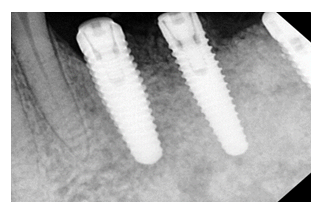

Figure 1: Clinical presentation of peri-implantitis at baseline showing inflammation, probing depth, and bone loss prior to intervention.

Figure 2: Clinical condition at 6-month follow-up demonstrating resolution of inflammation, reduced probing depth, and radiographic evidence of bone regeneration following GBR therapy.